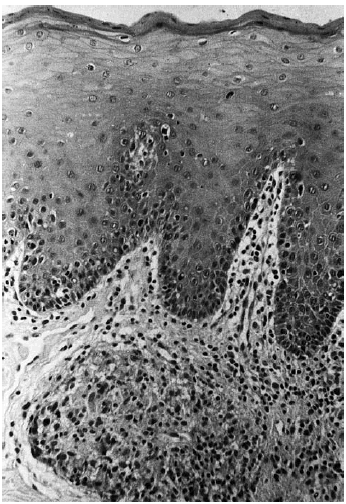

Practicada biopsia del labio superior se observó un epitelio normal con ligera exocitosis, la dermis mostró un infiltrado perivascular superficial y profundo, compuesto fundamentalmente por linfocitos; además, en la dermis profunda se pudo observar la formación de granulomas y en la dermis más superficial se vio un granuloma perfectamente delimitado sin caseosis central formado principalmente por histiocitos (fig. 2).

Fig. 2.--En dermis superficial granuloma perfectamente delimitado sin caseosis central.